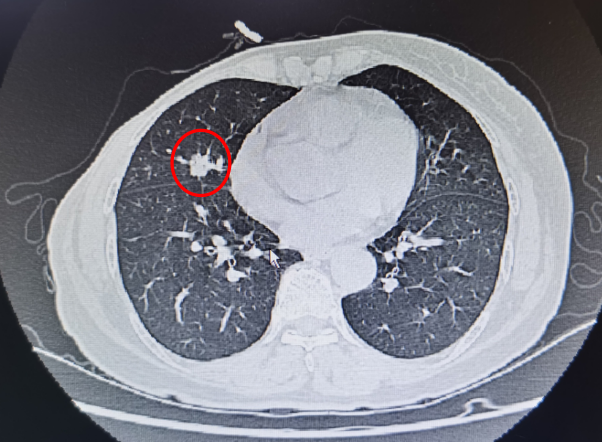

前段时间,一位李阿婆在家人陪伴下,来到惠州市中心人民医院肿瘤内科孙爱华副主任医师门诊复诊。李阿婆既往有乳腺癌病史,在肿瘤内科精心治疗下,病情近年来一直维持稳定。此次复诊检查发现肿瘤标志物CEA(癌胚抗原)有升高,肺部CT发现肺内有一新出现的小结节,直径约1cm大小。孙主任医师拿到检查结果后立即警惕起来,肺内这个小结节是乳腺癌复发后的肺内转移,还是新发的恶性肿瘤-肺癌?

孙主任当即告知李阿婆家属,建议进一步完善经皮肺穿刺活检术以明确病理诊断。因为李阿婆肺内新发的结节就长在心脏旁,直径仅约1cm,穿刺过程中稍有偏差就可能刺破心脏造成不可挽回的后果。患者家属一方面担心穿刺风险,另一方面又想尽快弄清楚病情,通过各种途径咨询省内多个三甲医院,得到的回复出奇的一致:建议行肺穿刺,但穿刺风险极大,穿刺成功机率极小。最后家属信任并选择了市中心人民医院肿瘤内科,决定在此做肺穿刺。

本例患者肺部CT图片提示靠近心脏处有一孤立的肺结节(如图所示)